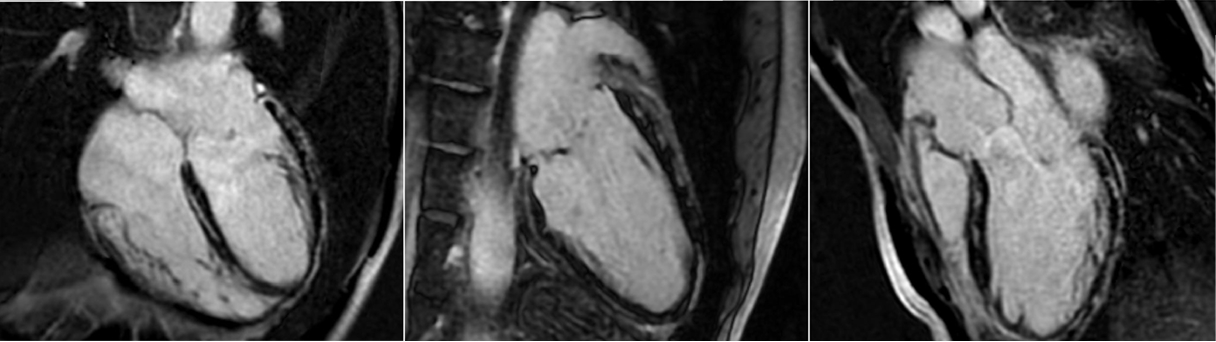

Fifty shades of grey

Caso condiviso da Marcello De Santis

La velocità di progressione della fibrosi cardiaca: un nuovo orizzonte

La velocità di progressione della fibrosi cardiaca emerge come un nuovo e cruciale indicatore prognostico nella cardiomiopatia ipertrofica. Un recente studio evidenzia come l’LGE rate sia più predittivo degli eventi avversi rispetto alla semplice estensione della fibrosi, aprendo nuove prospettive per il monitoraggio e la gestione terapeutica dei pazienti.